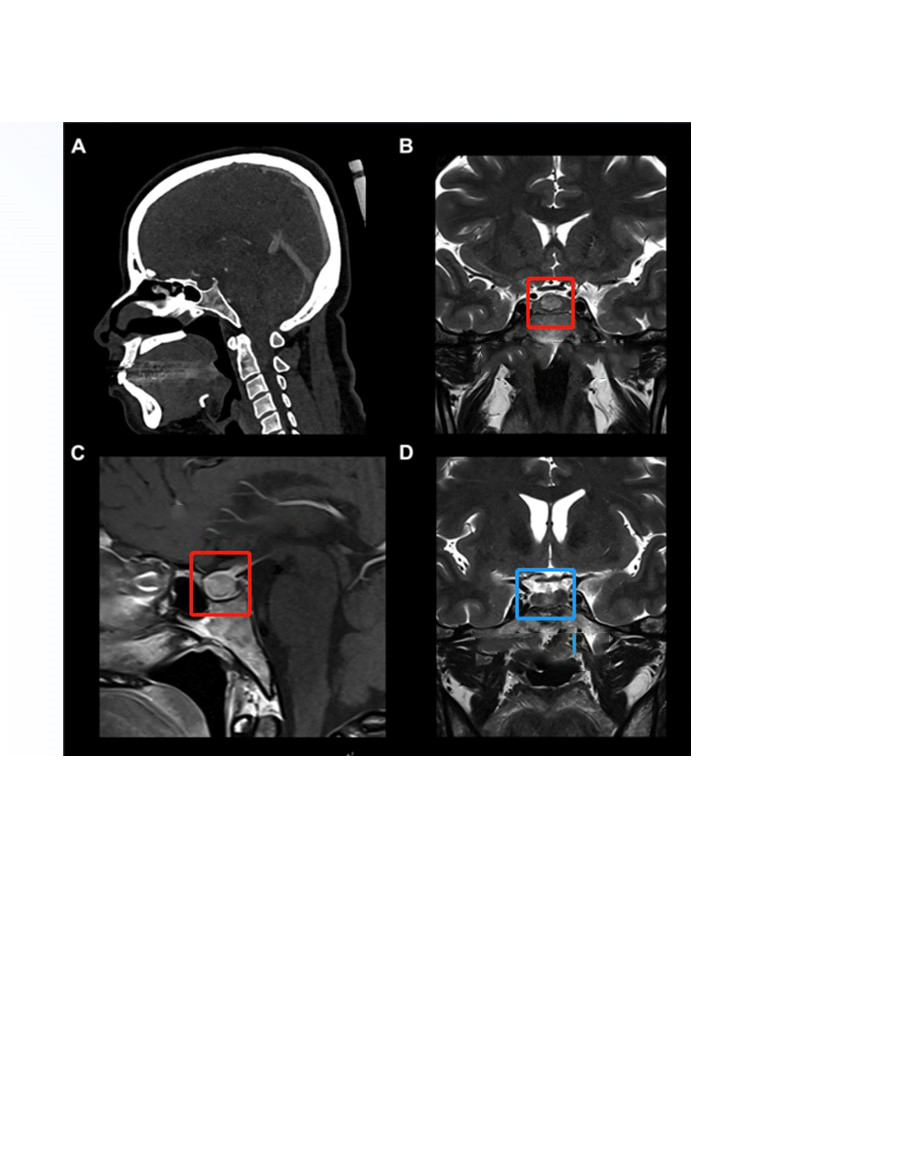

进行什么样的手术?经鼻内镜微创手术

神经内镜下经鼻-蝶窦垂体瘤切除术是在显微外科手术的基础上发展起来的,神经影像学(CT/MR)的进步,使得中小垂体瘤能够早期发现。虽然神经内镜系统大多应用于脑室内病变的治疗,但经过器械改进和临床经验积累,目前也可应用内镜单独(NE)手术或内镜辅助显微外科手术(NAM)经鼻-蝶窦行垂体瘤切除术。该手术方法的主要优点是创伤小,内镜通过鼻腔进入,不需要分离鼻中隔。Jho等(1997)报告了48例在内镜辅助下进行显微外科手术。

一名37岁的法国女性被发现有位于蝶鞍中央的9mm垂体瘤后,同样选择的也是神经内镜经鼻单鼻孔切除术,医生采用的是当前热门神经内镜“筷子手法”使肿瘤得以完整切除,目前正在进行相关内分泌治疗,手术后3年垂体瘤没有复发的迹象,无其他并发症。